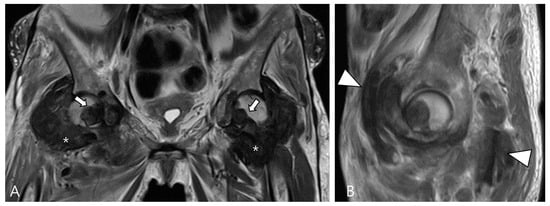

3.1.1. Hemosiderotic Synovitis

- Ando, T.; Kato, H.; Kawaguchi, M.; Nagano, A.; Hyodo, F.; Matsuo, M. MR imaging findings for differentiating nonhemophilic hemosiderotic synovitis from diffuse-type tenosynovial giant cell tumor of the knee. Jpn. J. Radiol. 2021, 39, 76–83. [Google Scholar] [CrossRef]